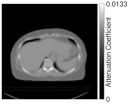

II-E2 Y90 PET/CT physical phantom measurements and patient scan

For training BCD-Net, we used PET measurements of a sphere phantom (Fig. 4) where six ‘hot’ spheres (2,4,8,16,30 and 113 mL, 0.5 MBq/ml) are placed in a ‘warm’ background (0.057 MBq/ml) with total activity of 0.65 GBq. The phantom was scanned for 40 (3 acquisitions) - 80 (1 acquisition) minutes on a Siemens Biograph mCT PET/CT. For testing BCD-Net and other reconstruction algorithms, we used an anthropomorphic liver/lung torso phantom (Fig. 4) with total activity and distribution that is clinically realistic for imaging following radioembolization with Y-90 microspheres: 5% lung shunt, 1.17 MBq/mL in liver, 3 hepatic lesions (4 and 16 mL spheres, 29 mL ovoid) of 6.6 MBq/ml. The phantom with total activity of 1.9 GBq was scanned 5 times (each 30 minutes) on a Siemens Biograph mCT PET/CT. Fig. 4 and Table II provide details on the count-level (random fraction) and activity distribution differences between training (sphere phantom) and testing (liver phantom) dataset. We also tested BCD-Net with an actual Y-90 patient scan and Table III provides count-level information.

We acquired all measurement data with time of flight TOF information. The measurement data size is 20016862113. The last dimension of measurement indicates the number of time bin. The reconstructed image size is 200200112 with a voxel size 4.074.072.03 (mm3). To reconstruct the image with measurement data, we used a SIEMENS TOF system model ( in (1)) along with manufacturer given attenuation/normalization correction, PSF modelling, and randoms/scatters estimation.

| Sphere phantom attenuation map (coronal) | Attenuation map (axial) | True activity image | of regularized methods (EM) |

![]() |

| Liver phantom attenuation map (coronal) | Attenuation map (axial) | True activity image | of regularized methods (EM) |